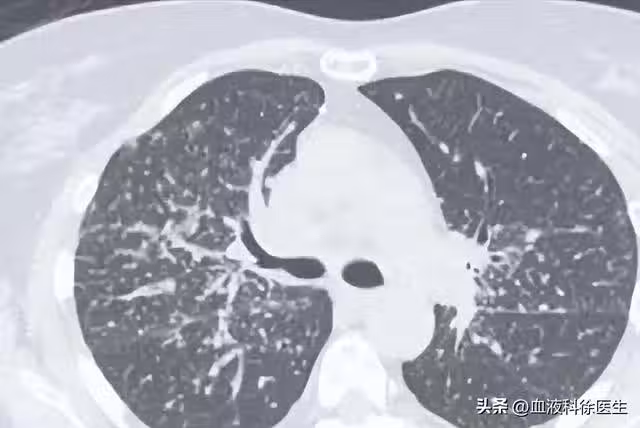

55歲男子5月體檢發現肺結節,年底就肺癌晚期,醫生:警惕肺結節

這便可以解釋為什麼王叔叔身邊的許多同事也被發現有肺結節,因為肺結節的發病率在人群中確實不低,預計隨著吸菸、空氣污染及人口老齡化的影響,檢出率會進一步升高。

一、早期肺癌——肺結節的病因